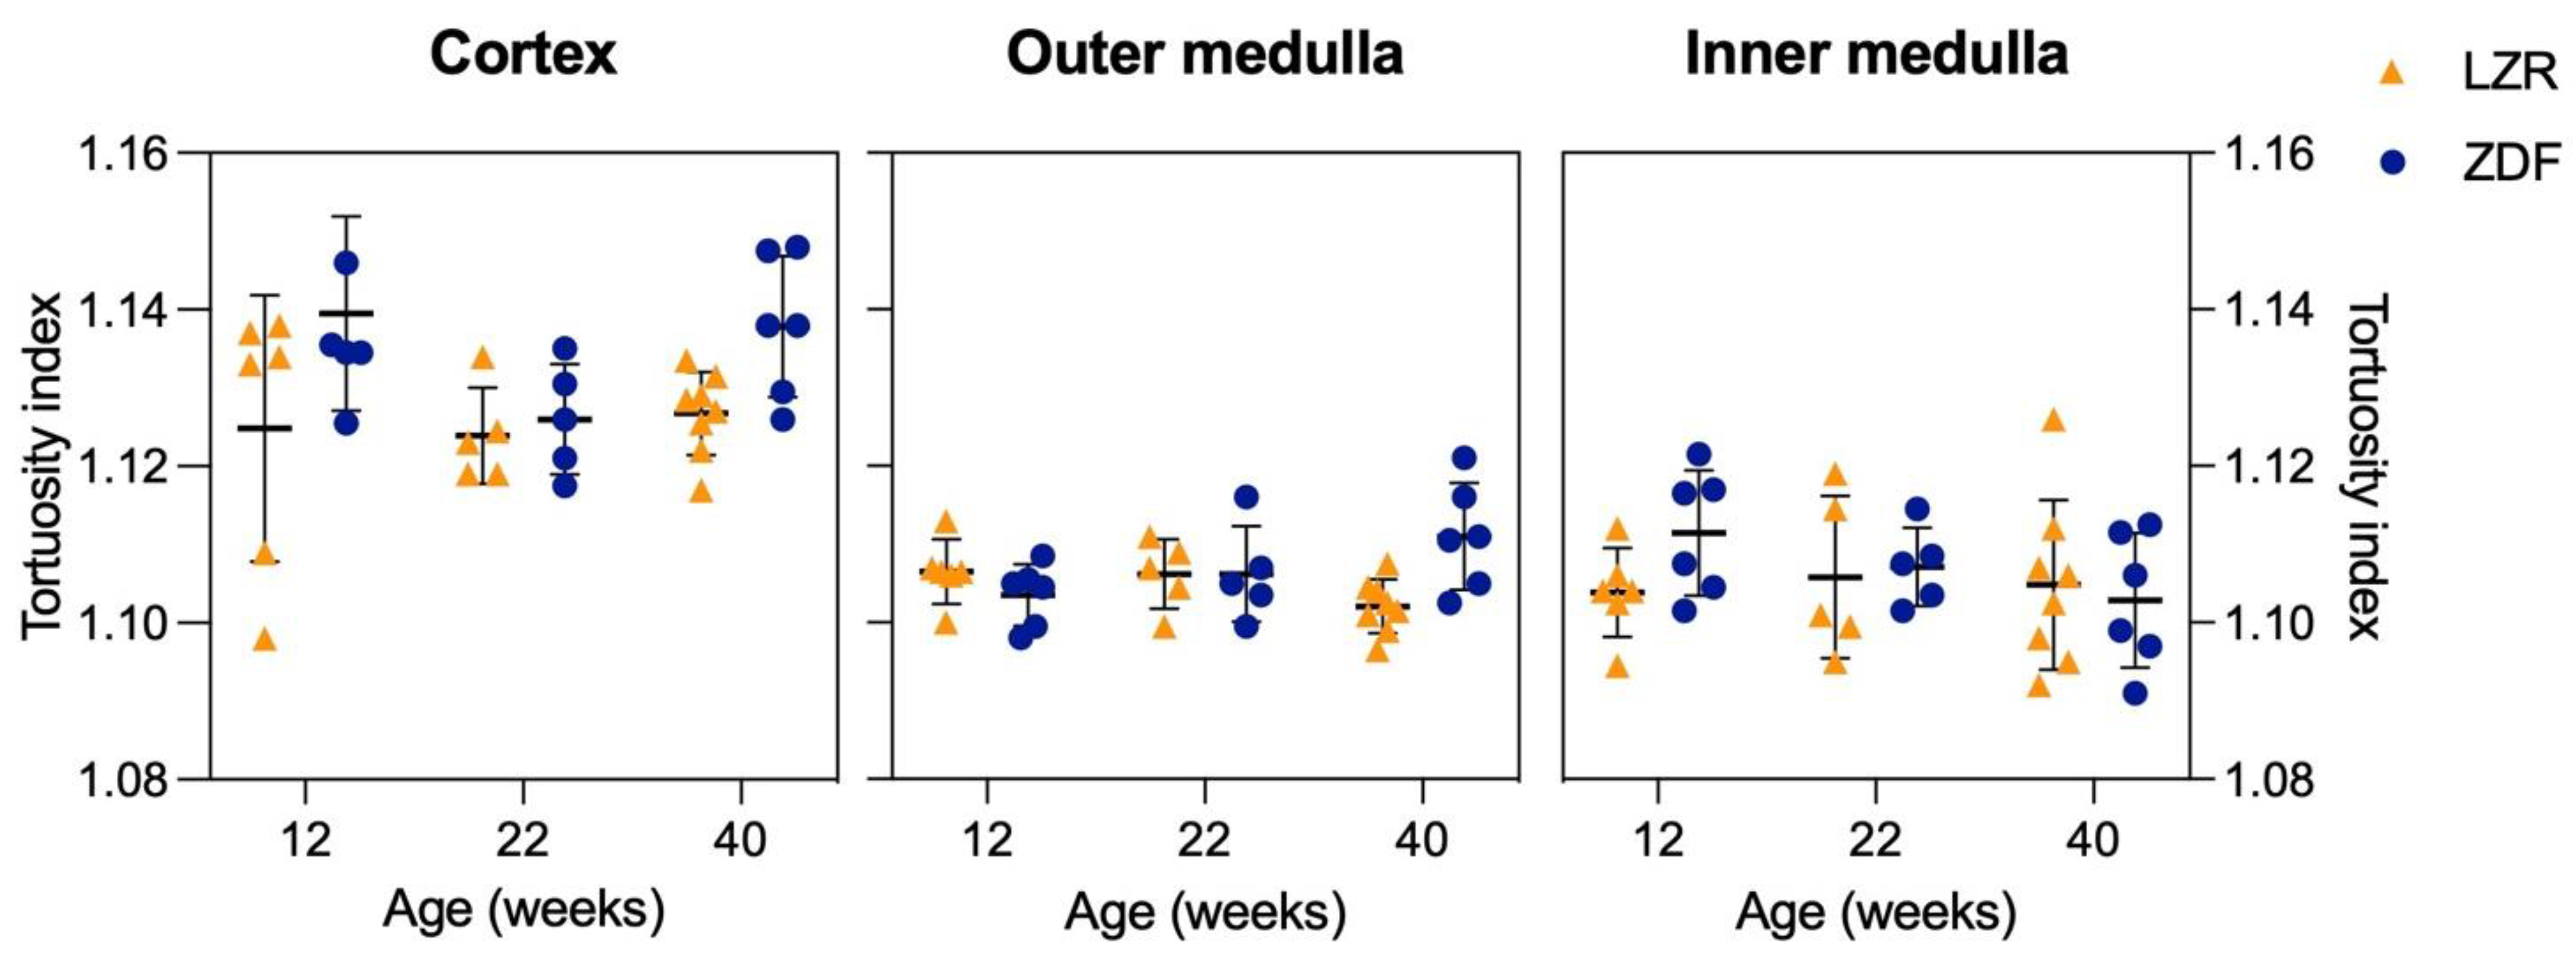

3.3. Quantified Measurements from SRUS

3.4. Qualitative and Quantitative Assessment in µCT